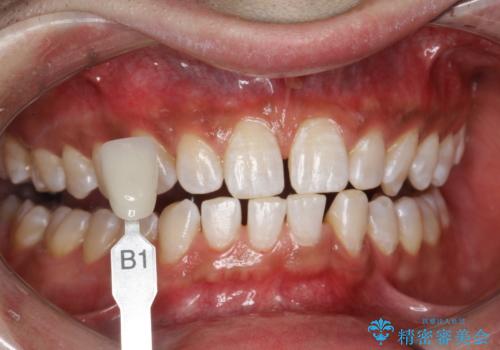

- ホワイトニングで、できる限り白くしたいとのことで来院されました。処置前クリーニング(¥3,300)・エクセレントホワイトニング(¥29,700)・トリートメント(¥550)を行いました。